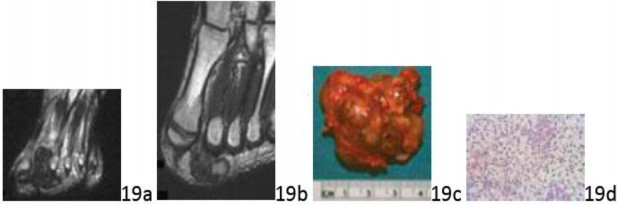

Question 19 A 25-year-old man has a painful mass in a web space of his foot. MRI scans are seen in Figures 19a (T2 STIR) and 19b (T1), a representative gross specimen is seen in Figure 19c, and a H&E stain is seen in Figure 19d. What is the most likely diagnosis?

Question 19 A 25-year-old man has a painful mass in a web space of his foot. MRI scans are seen in Figures 19a (T2 STIR) and 19b (T1), a representative gross specimen is seen in Figure 19c, and a H&E stain is seen in Figure 19d. What is the most likely diagnosis?

1. ## Melanoma

2. ## Synovial sarcoma

3. ## Interdigital neuroma

4. ## Epithelioid sarcoma

5. ## Giant cell tumor of tendon sheath

DISCUSSION: Giant cell tumors of tendon sheath are common in the hands and feet. Because of significant hemosiderin deposition, they commonly appear hypointense to skeletal muscle on both T1 and T2 pulse-weighted sequences. The hemosiderin is manifested in the brownish discoloration in the gross specimen. The photomicrograph shows bland spindled stromal cells and abundant multinuclear giant cells. Treatment is marginal excision with relatively low rates of tumor recurrence. Although the foot is not an infrequent site of melanoma and there are some shared radiologic features with giant cell tumor of tendon sheath, histologically melanoma is composed of cells both spindled and epithelioid arranged in nests or clusters. Synovial sarcoma is the most common sarcoma of the foot which radiographically has mineralizations in 30% of cases. It is typically heterogeneous on both MR pulse sequences. Microscopically, monophasic synovial sarcoma contains spindled cells that are arranged in short intersecting fascicles similar to fibrosarcoma. Pseudoglandular areas can be observed in biphasic cases.

Epithelioid sarcoma, though common in the hand, is relatively rare in the foot and is histologically distinct from giant cell tumor of tendon sheath. When this tumor secondarily involves bone, it may be confused with osteomyelitis.

Pref Res# 19 is 5.